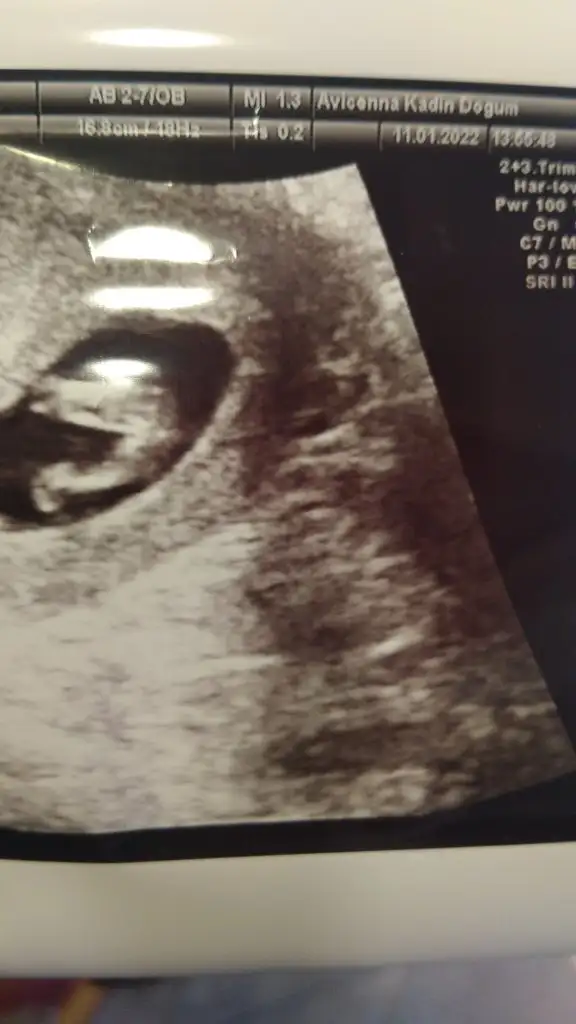

Merhaba ikra meyra hn yorum yapabilir misiniz? 🥰😘

Eklentiler

• 21793DEB-259F-411B-896E-9DD58B3FB36D.webp

21793DEB-259F-411B-896E-9DD58B3FB36D.webp

32,4 KB · Görüntüleme: 63